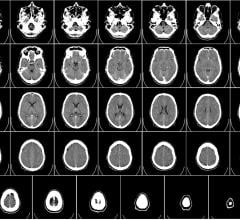

Time is brain. The longer a brain injury goes untreated, the higher the chance of permanent damage or death.